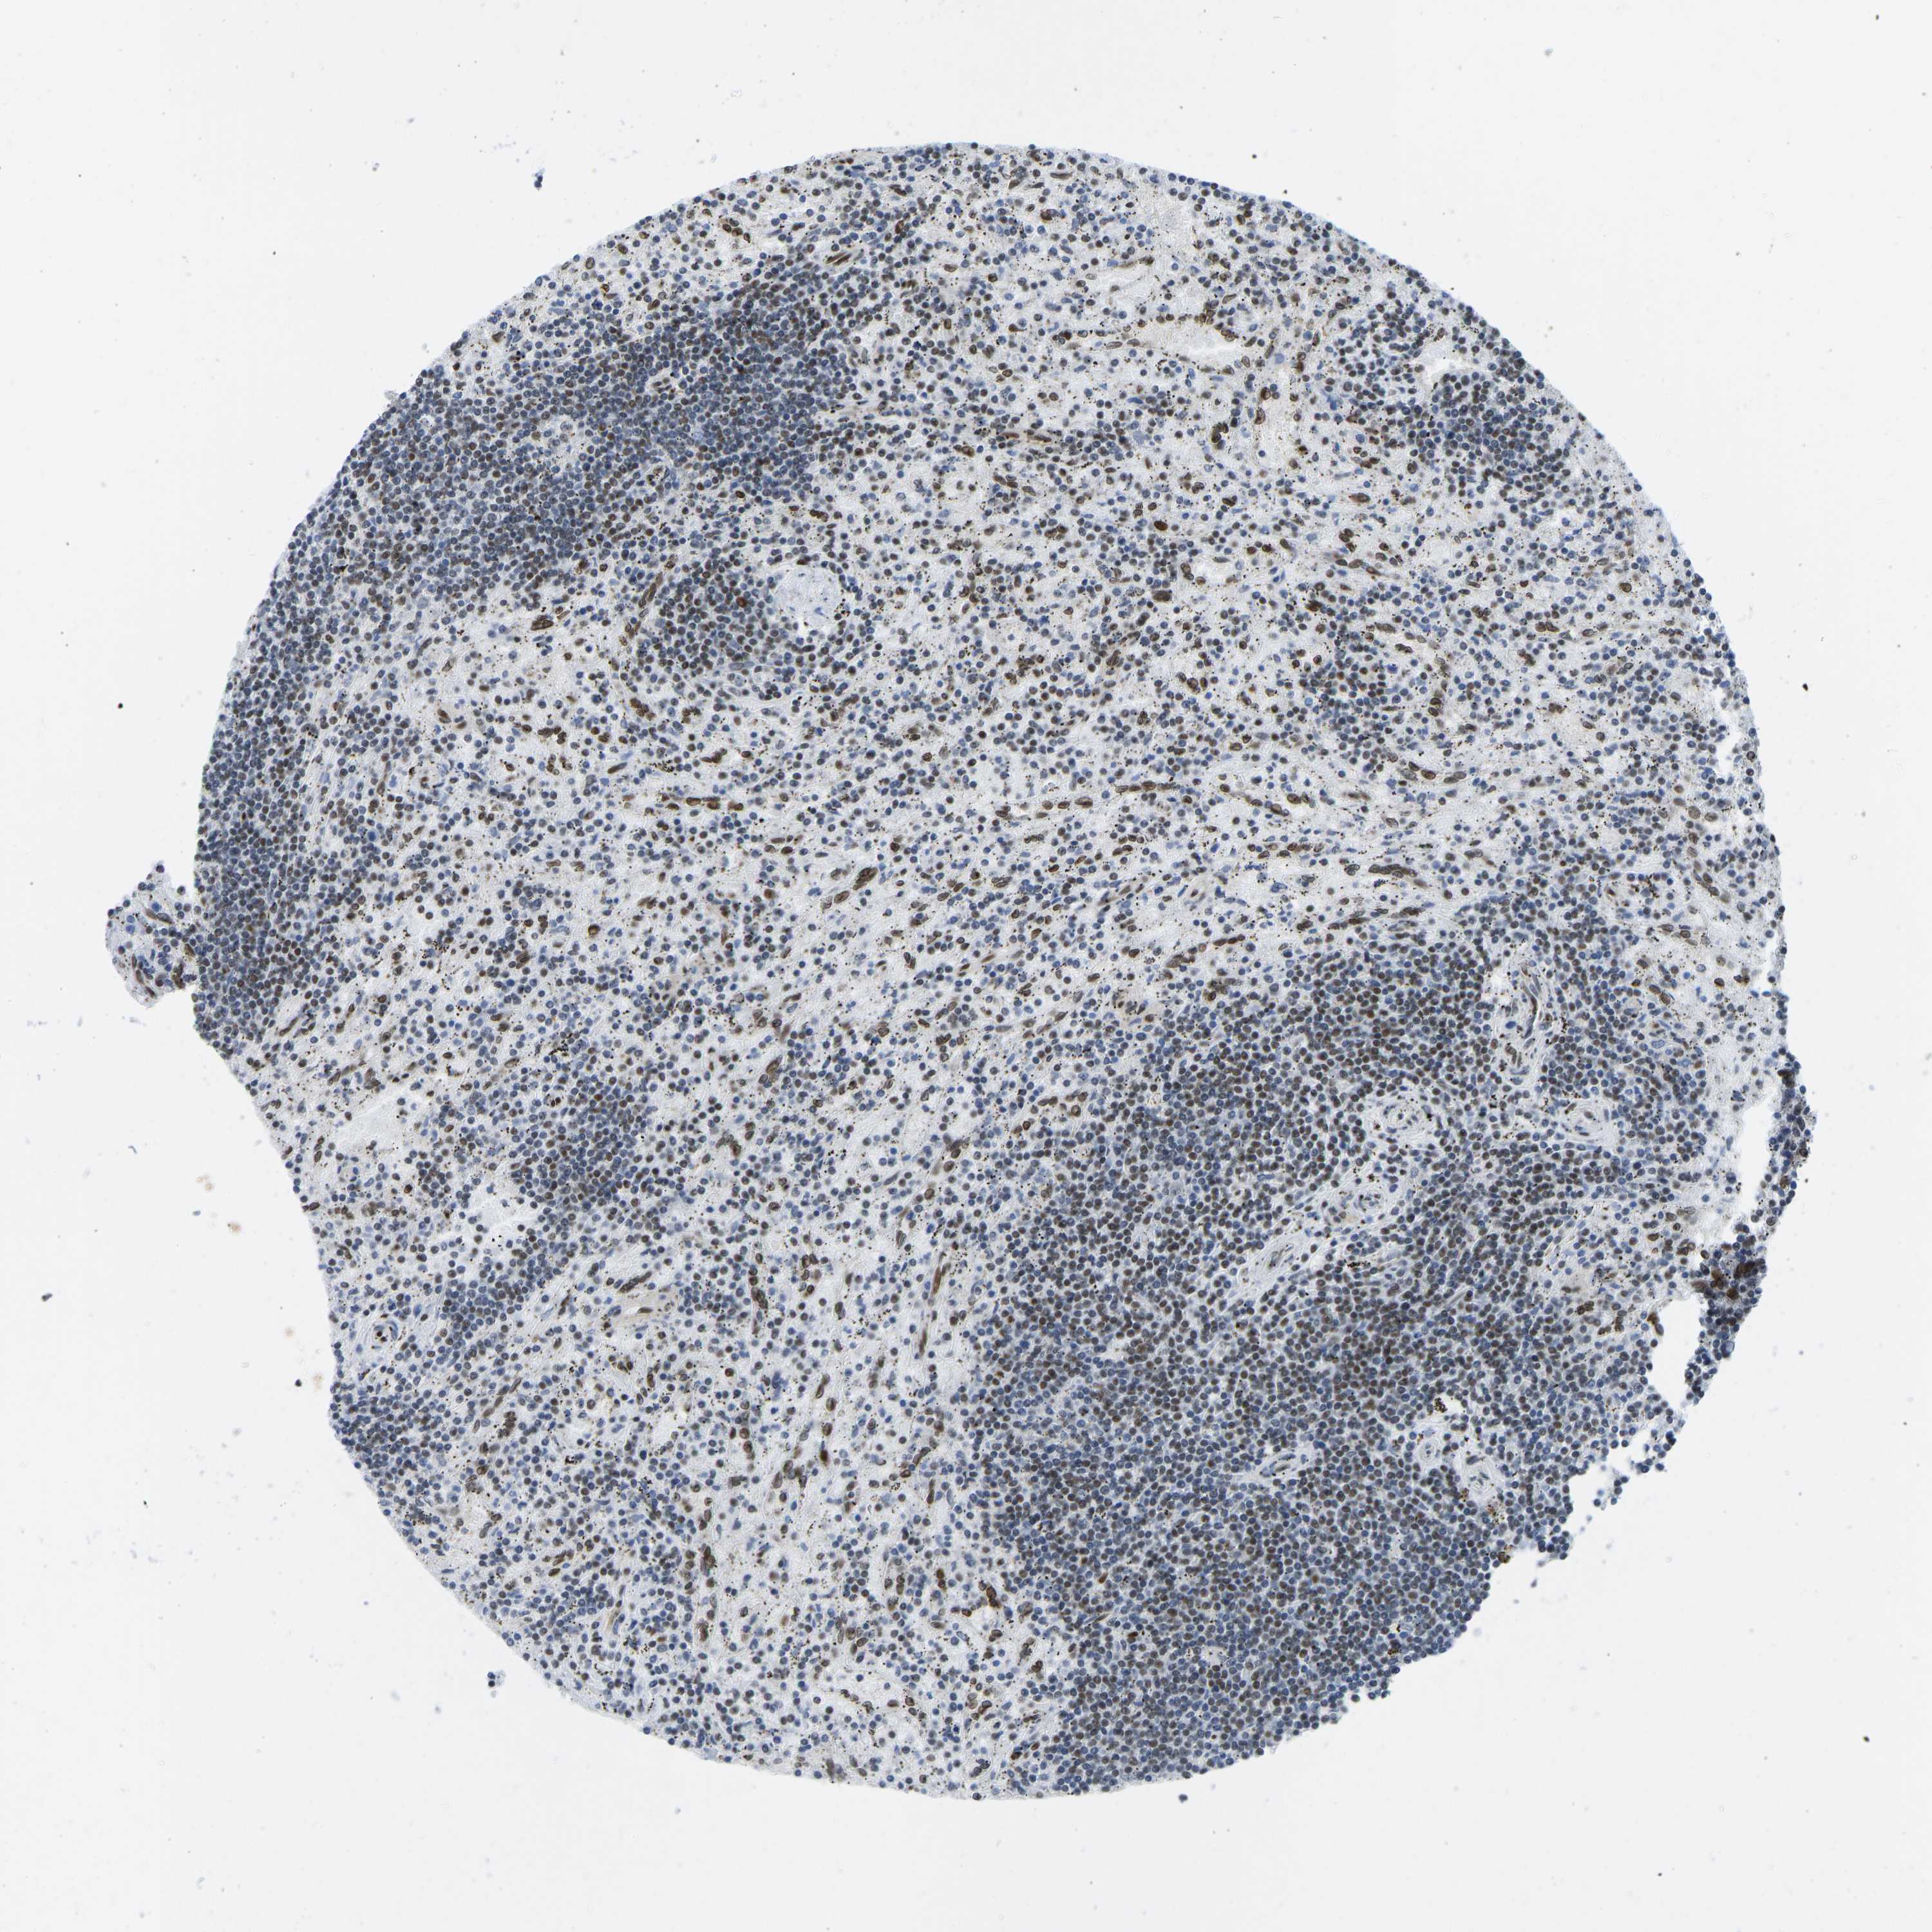

CANCER LYMPHOMA Show tissue menu

LYMPHOMA - Protein expressioni

A mouse-over function shows sample information and annotation data. Click on an image to view it in a full screen mode. Samples can be filtered based on level of antibody staining by selecting one or several of the following categories: high, medium, low and not detected. The assay and annotation is described here.

Antibody stainingi

Antibody staining in the annotated cell types in the current human tissue is reported as not detected, low, medium, or high, based on conventional immunohistochemistry profiling in selected tissues. This score is based on the combination of the staining intensity and fraction of stained cells.

Each image is clickable and will lead to virtual microscopy that enables deeper exploration of all samples and also displays staining intensity scores, fraction scores and subcellular localization as well as patient and tissue information for each sample.

Antibody HPA017998

Antibody HPA018864

Staining

High

Medium

Low

Not detected

Intensity

Strong

Moderate

Weak

Negative

Quantity

>75%

75%-25%

<25%

None

Location

Nuclear

Cytoplasmic/membranous

Cytoplasmic/membranous,nuclear

Hodgkin's disease, NOS

Malignant lymphoma, non-Hodgkin's type, High grade

Malignant lymphoma, non-Hodgkin's type, Low grade